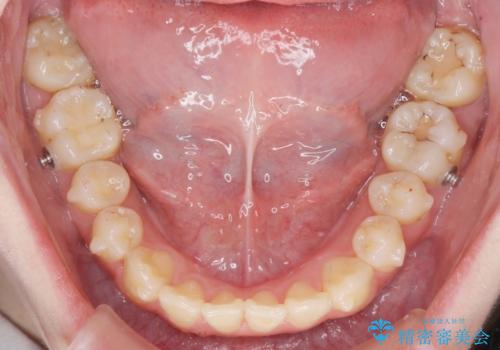

マウスピースで行う出っ歯の改善 後方移動

少し時間はかかりましたが、しっかりと綺麗な歯並びに仕上げることができ、大変喜んでいただくことができました。